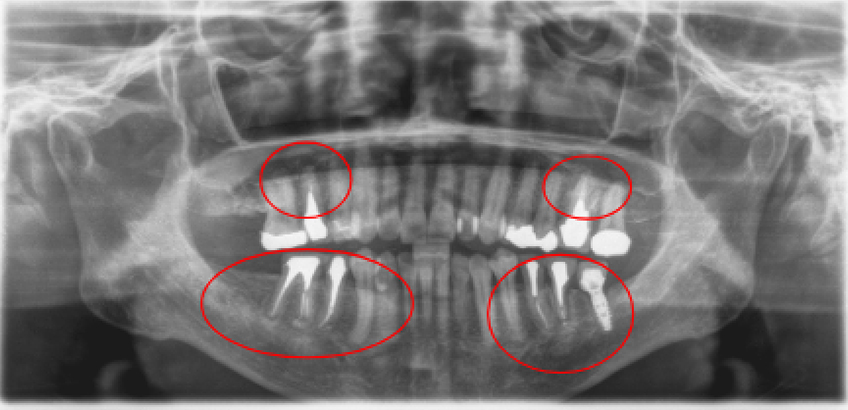

治療前治療後

| 治療内容 | インプラント奥歯1本・根管治療6歯 |

|---|---|

| 患者様の年齢 | 54歳 |

| 患者様の性別 | 女性 |

| 治療期間 | 2年 |

| 治療回数 | 根管治療合わせて70回程度 |

| 治療費用 | インプラント1歯 50万円/根管治療6歯 30万円 |

| 治療で得られるメリット |

|

| 治療する際に起こる リスク・副作用 |